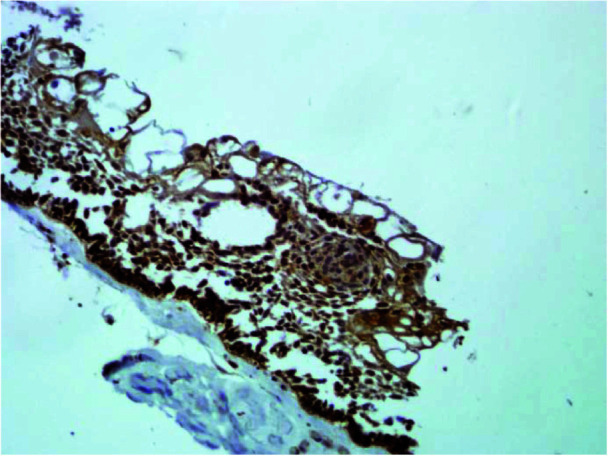

Results: The PXN marker was detected in the cytoplasm of tumor cells (unicystic and solid ameloblastoma) and the epithelial layer of cysts (DC and OKC). The intensively stained marker of PXN was observed in 9 cases (64.3%) of the DC, 14 cases (70%) of OKC, 12 cases (75%) of unicystic ameloblastoma, and 13 cases (72.2%) of solid ameloblastoma. However, there was not statistical difference of PXN protein expression between DC and OKC (p Value = 0.51) and unicystic and solid ameloblastoma (p = 0.58), also the same was true for cysts and tumors (p = 0.37).